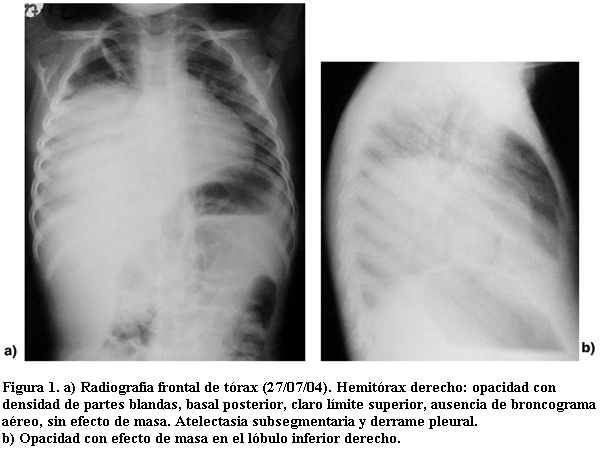

12 de agosto 2004. Consulta nuevamente por fatiga, se realiza nueva radiografía de tórax (figura 2), en la cual se observa extensa opacidad del hemitórax derecho, que es interpretada por el médico pediatra como neumonía extensa, con foco no resuelto. Se medica con vancomicina.